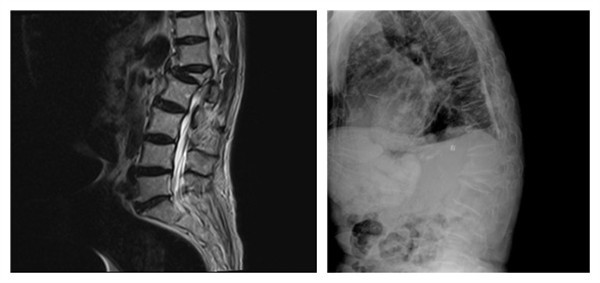

一月前,84岁刘某在家中突然摔倒,坐在地上,不能站起,家人扶起后感双下肢无力,不能行走,鉴于患者之前有脑梗病史,家属将其送至我院干二病区诊治。入院后详细追问病史,患者有冠心病心房纤颤病史30余年,高血压病史20余年,颞叶脑梗死病史10年。通过神经系统详细查体,考虑患者病情无脑部定位体征,考虑与腰椎病变有关。急扫腰椎MRI示:腰椎退行性变,L4/L5、L5/S1椎间盘膨出,L1椎体压缩性骨折,T12-L2水平脊髓信号异常,考虑损伤。

术前腰椎MRI及术前腰椎侧位片